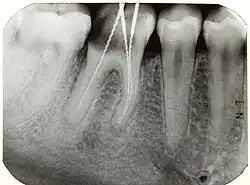

Röntgenmessaufnahme an Zahn 46; drei Wurzelkanäle

Hierbei wird eine Röntgenaufnahme des zu behandelnden Zahnes angefertigt, während sich in diesem ein röntgendichter Gegenstand befindet, beispielsweise eine Hedströmfeile oder ein Silberstift, der bis zur vermuteten beziehungsweise taktil gefundenen Arbeitslänge eingeführt wurde. Auf diese Weise kann die Übereinstimmung der vermuteten Arbeitslänge mit der röntgenologischen Wurzelspitze bestimmt werden, die jedoch aufgrund der Projektion einer dreidimensionalen Struktur in eine zweidimensionale Ebene nicht zwingend mit der anatomischen Wurzelspitze übereinstimmen muss. Der endodontische Apex (auch physiologischer Apex), eine Einziehung der Pulpa, liegt ca. 1–2 mm vor (coronal) dem anatomischen Apex.[1]